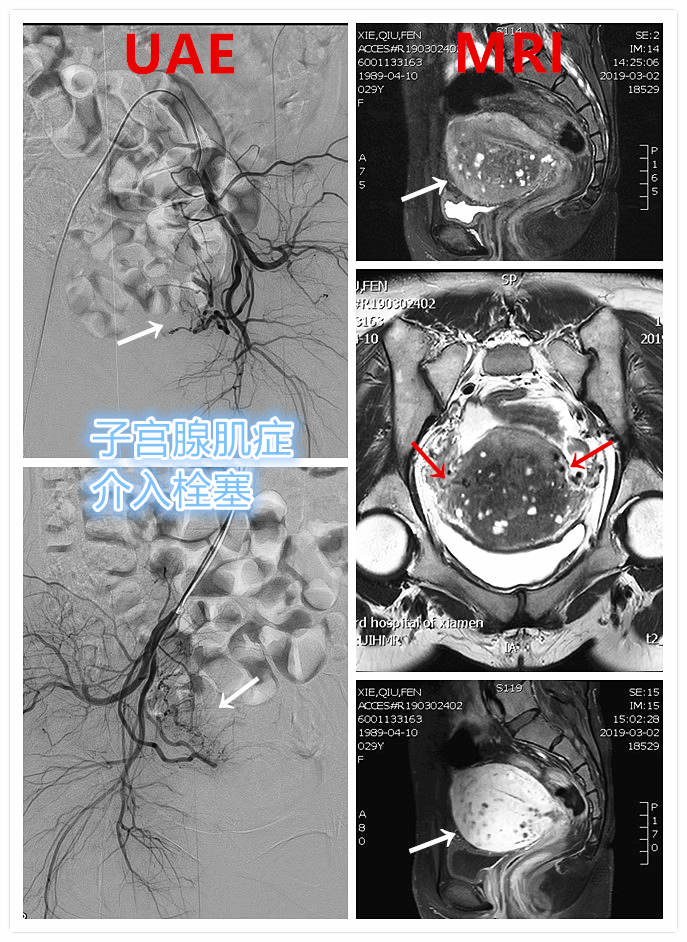

典型病例

例1

青年女性患者,痛经近10年,近5年痛经明显加重。确诊为子宫腺肌症(弥漫型),经放置曼月乐、注射亮丙瑞林等妇科保守治疗,症状缓解不理想,痛经进行性加重,严重困扰工作与生活。

- 行子宫腺肌症介入栓塞治疗

- 插管至右侧髂内动脉造影,显示右侧子宫动脉

- 插管至右侧子宫动脉,显示子宫右侧病灶情况

- 插管至左侧子宫动脉,显示子宫左侧病灶情况

- 术前MRI显示子宫明显增大,病灶主要位于子宫前壁

术前MRI显示子宫明显增大,病灶主要位于子宫前壁

- 患者术后1个月痛经明显缓解。术后3个月复查MRI显示子宫明显缩小,前壁病灶萎缩坏死。

术后3个月复查MRI显示子宫明显缩小,前壁病灶萎缩坏死